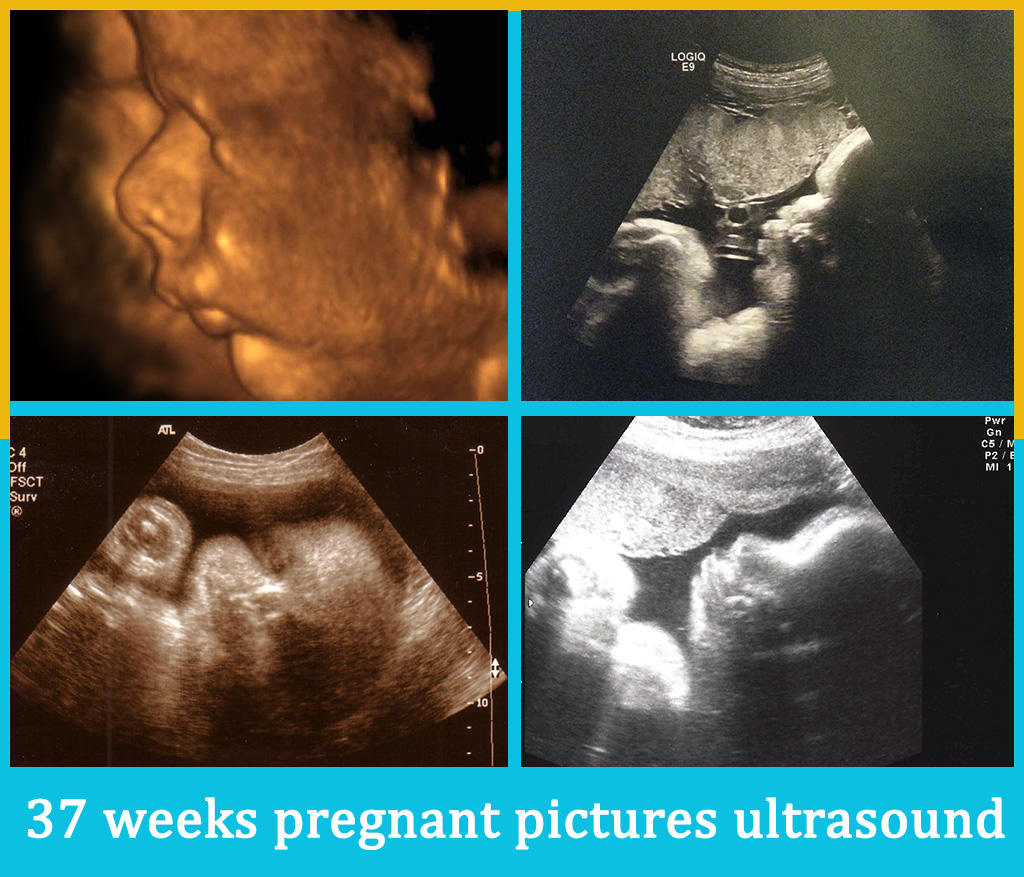

List showcases captivating images of real life 37 week fetus pictures galleryz.online

real life 37 week fetus pictures

Human Fetus At Week 37 Of Gestation Photograph by Sebastian Kaulitzki …

37 Weeks Pregnant: Symptoms, Baby Weight and Preparing for Labour …

Fetal development – 37 weeks pregnant – BabyCenter Canada

Pregnancy Weeks 37-42: Symptoms & Fetus Growth Stages

Pregnancy Weeks 37-42: Symptoms & Fetus Growth Stages

Pregnancy week 37 – you and your baby | mother-top.com

Human fetus – week 37 stock illustration. Illustration of uterus – 58830075

Weekly development of a human fetus – week 37.

Normal 37 weeks pregnancy and ultrasound, your complete guide …